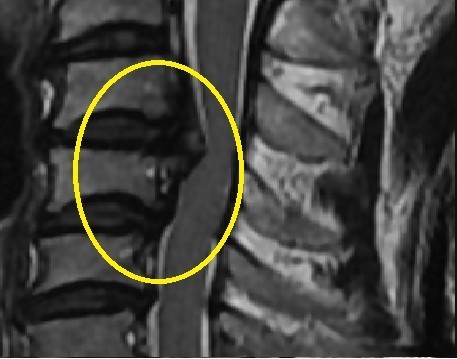

후종인대 골화증은 척추의 뒤쪽에 있는 후종인대가 뼈처럼 단단해지면서 척추관을 좁히거나 신경을 압박하는 질환입니다. 후종인대는 척추뼈 사이를 연결하는 인대로, 척추의 안정성을 유지하는 역할을 합니다. 후종인대 골화증은 주로 경추에서 발생하며, 흉추와 요추에서도 발생할 수 있습니다.

후종인대 골화증의 증상은 척추관을 좁히거나 신경을 압박하는 정도에 따라 다릅니다. 증상이 경미한 경우에는 증상이 없거나 가벼운 통증이나 불편감만 느낄 수 있습니다. 증상이 심한 경우에는 다음과 같은 증상이 나타날 수 있습니다.